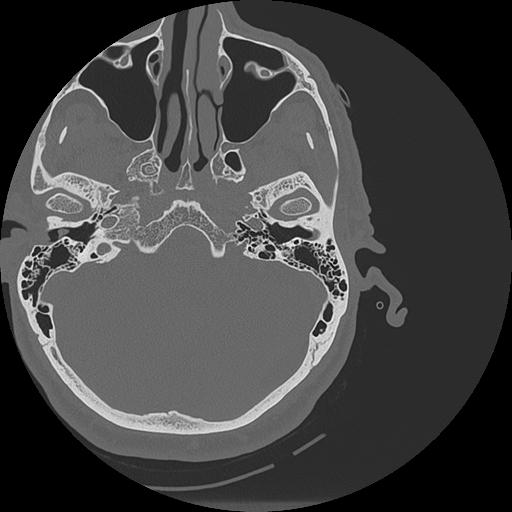

7 HUESO,,Vol,0.5,HUESO,,